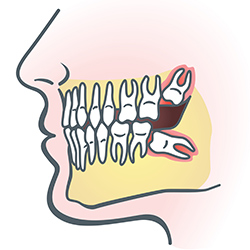

wisdom teethWisdom teeth are types of molars found in the very back of your mouth. These teeth usually appear in late teens or early twenties but may become impacted (fail to erupt) due to lack of room in the jaw or angle of entry. When a wisdom tooth is impacted, it may need to be removed. If it is not removed, you may develop gum tenderness, swelling, or even severe pain. Impacted wisdom teeth that are partially or fully erupted tend to be quite difficult to clean and are susceptible to tooth decay, recurring infections, and even gum disease.

Wisdom teeth are typically removed in the late teens or early twenties because there is a greater chance that the teeth's roots have not fully formed and the bone surrounding the teeth is less dense. These two factors can make extraction easier, as well as making the recovery time much shorter.

In order to remove a wisdom tooth, your dentist first needs to numb the area around the tooth with a local anesthetic. Since the impacted tooth may still be under the gums and imbedded in your jaw bone, your dentist will need to remove a portion of the covering bone to extract the tooth. In order to minimize the amount of bone that is removed with the tooth, your dentist will often "section" your wisdom tooth so that each piece can be removed through a small opening in the bone. Once your wisdom teeth have been extracted, the healing process begins. Healing time varies depending on the degree of difficulty related to the extraction. Your dentist will share with you what to expect and provide instructions for a comfortable, efficient healing process.